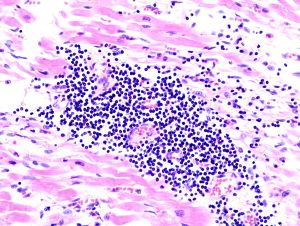

صورة نسيجية لالتهاب فيروسي لعضلة القلب في عملية تشريح لمريض مصاب بالمرض. | |

يتم كشف التهاب العضلة القلبية عن طريق استخدام مخطط القلب الكهربائي(ECG)،وهناك أيضاً علامات للالتهاب من عدم انتظام تركيز الكرياتين (creatine)، والتروبونين (troponin). ويمكن كشفها أيضاً عن طريق عمل القسطرة، بحيث يتم عمل فحص لنسيج القلب، بحيث يتم أخذ عينة صغيرة من النسيج الداخلي والخارجي للقلب، ويتم فحصها من قبل مختص أمراض من خلال مجهر ضوئي. حديثاً، أصبح بالإمكان الكشف من خلال استخدام جهاز الأشعة المغناطيسية لمنطقة القلب (cMRI: Cardiac Magnetic Resonance Image)، وقد تبين أنها طريقة نافعة.